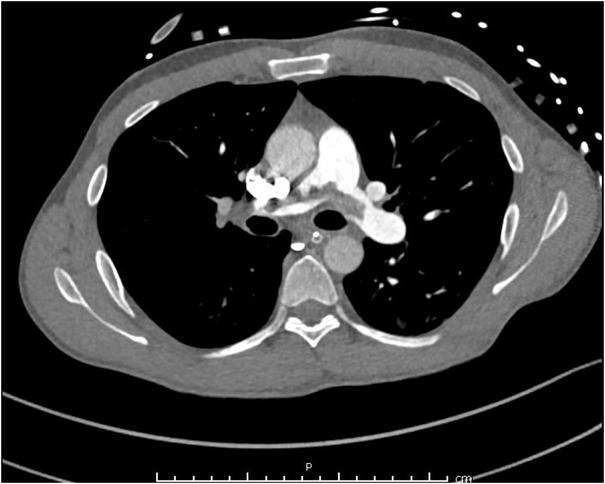

A previously healthy 46-year-old male, on no medications, presented following a pulseless electrical activity (PEA) arrest after collapsing at home. He was resuscitated and had the return of spontaneous circulation before arriving at the nearby tertiary care hospital. The patient underwent a CT pulmonary angiogram and CT of the abdomen and pelvis which demonstrated large saddle PE (Figure 1) with a significant burden of thrombus extending into both right and left pulmonary artery circulations. Evidence of right heart strain was demonstrated on a bedside echocardiogram. The patient was treated with therapeutic anticoagulation with an intravenous heparin sodium (Pfizer, Sydney, Australia) infusion, insertion of an IVC filter and pulmonary rheolytic thrombectomy. He was subsequently managed in intensive care while intubated, requiring minimal inotropic support with intravenous norepinephrine (Pfizer, Sydney, Australia) infusion.

CT pulmonary angiogram axial image demonstrating saddle pulmonary embolism